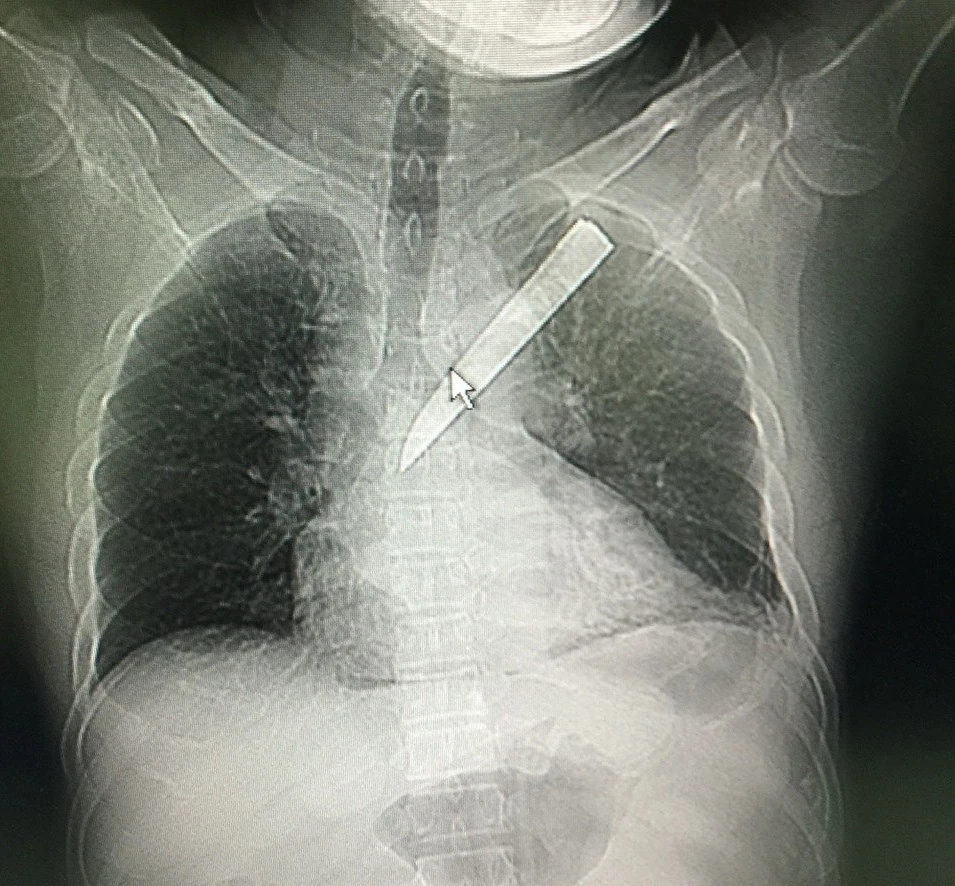

Lưỡi dao gãy xuyên ngực bệnh nhân.

Trước đó, ngày 3-1, trong lúc ẩu đả, ông Kỳ bị đâm một nhát vào ngực trái bằng dao Thái Lan, lưỡi dao gãy nằm trọn trong lồng ngực. Ông được đưa đến cấp cứu tại Trung tâm Y tế huyện Gò Dầu. Sau đó, bệnh nhân được chuyển đến BV Xuyên Á trong tình trạng đau đớn dữ dội, khó thở. Kết quả khám lâm sàng và chụp CT xác định bệnh nhân bị vết thương thấu ngực trái, có tổn thương màn tim, tràn dịch phổi.

“Ngay lập tức, bệnh nhân được phẫu thuật cấp cứu để xác định tổn thương và cầm máu. Khi mở ngực bệnh nhân, các bác sĩ thấy lưỡi dao xuyên thủng phổi, gây tổn thương màn tim. Sau khi lấy dao, các bác sĩ cầm máu kỹ lưỡng các tổn thương ở phổi và tim, đặt dẫn lưu màn phổi” - TS-BS Châu nói.